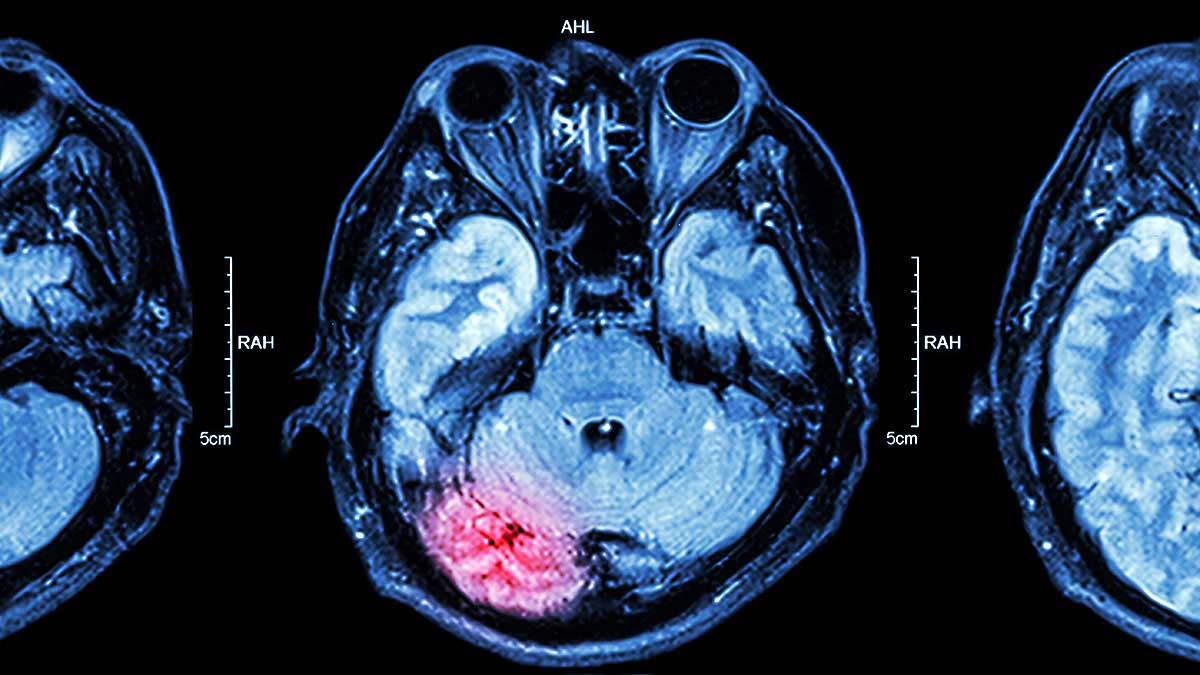

Traumatic Brain Injury (TBI) is an invisible but widespread epidemic. Over 27 million people worldwide suffer a TBI each year—many due to motor vehicle accidents (MVAs), falls, or blunt-force trauma. The vast majority of mild TBIs, such as concussions, go undiagnosed because symptoms like headaches, fatigue, mood changes, or memory issues can take days or weeks to emerge.

At Allied Neurology in Englewood, NJ, we use cutting-edge tools to detect brain trauma early, even when conventional ER tests show nothing:

- Diffusion Tensor Imaging (DTI) MRI